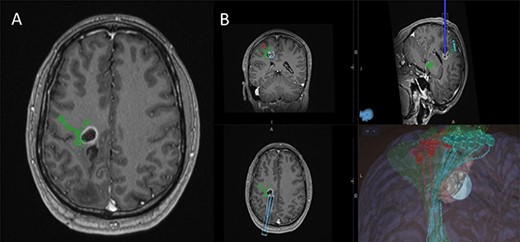

(A) Axial T1-weighted image with gadolinium showing the lesion with imposed DTI tractography of the CST; (B) planned trajectory for insertion of the tubular retractor guided by the preoperative integrated anatomical and functional motor mapping.

5-Aminolevulinic Acid (5-ALA) was given orally 2 h before the surgery. The least disruptive trajectory was selected taking into account the previous biopsy and the preoperative mapping information (Fig. 3). Under Stealth guidance, a skin incision was made overlying the planned craniotomy site. After the craniotomy, the dura was opened and a subdural strip of electrodes was placed over the primary motor cortex. Replicable motor responses from the hand muscles were obtained at 7 mA current intensity (Fig. 4). Motor evoked potentials (MEPs) were obtained continuously throughout the procedure. A transsulcal parafascicular approach was used. The sulcus was opened sharply under the microscope. At the depth of the sulcus, a preselected tubular retractor (NICO BrainPath 75 mm × 13 mm) was passed to the superficial surface of the lesion. While performing brain cannulation to the lesion, a monopolar probe (INOMED©) navigated with SureTrack (MEDTRONIC©) was used to perform continuous subcortical stimulation, train-of-five technique using high-frequency stimulation.